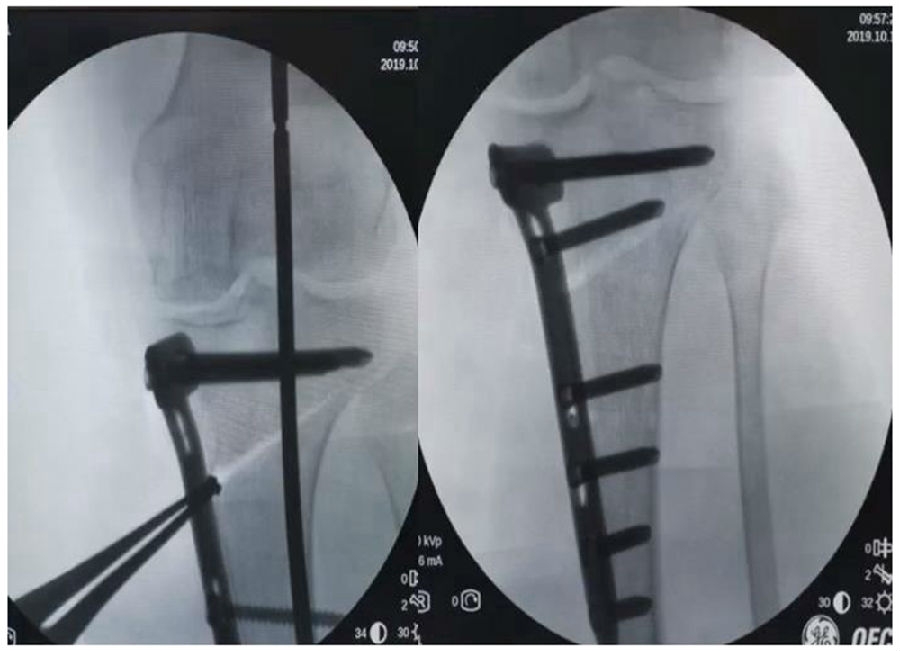

(3)Ⅲ型骨折

首先要把截骨撑开钳拿下来,此时骨折端会自动复位,然后再由外向内侧打入一颗拉力螺钉,将胫骨平台做临时固定,然后再进一步的用摆锯锯或是用骨刀打,保留1cm的合页,最后再进行撑开,做内固定。同样要求患者做结构植骨加延迟负重。

截骨偏前,截骨线过短;Ⅲ型骨折;保留1cm合页

结构植骨,外侧拉力钉固定